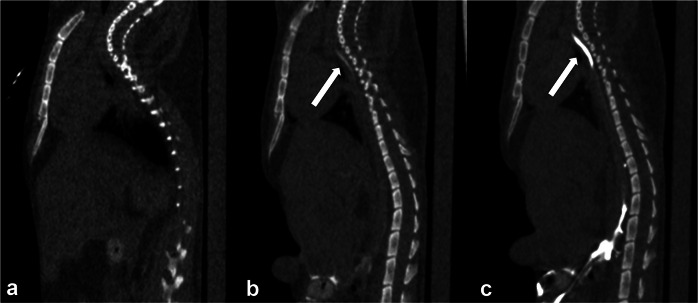

Methods: Twelve female BALB/c mice were injected with 35 μL of iodinated contrast medium (iomeprol 350 mgI/mL) into the mesenteric (mesenteric group) or popliteal (popliteal group) lymph nodes. CT images were acquired before injection and 1 min, 3 min, 5 min, 10 min, and 15 min after injection using a micro-CT scanner. Contrast ratios (CRs) were measured at the cisterna chyli and three levels of the TD (diaphragm, carina, and venous angle). Two experienced radiologists qualitatively assessed images as good, fair, or poor.

Results: The mesenteric group had significantly higher mean (± standard deviation) CRs than the popliteal group for all examined regions at 1 min after injection: cisterna chyli (14.01 ± 4.77 versus 1.47 ± 1.21, p < 0.001), diaphragm (7.28 ± 2.50 versus 0.85 ± 0.61, p = 0.0011), carina (10.33 ± 3.42 versus 0.44 ± 0.40, p < 0.001), and venous angle (6.26 ± 2.02 versus 0.79 ± 0.75, p < 0.001). For the TD between the cisterna chyli and the diaphragm, 6/6 mice in the mesenteric group showed strong enhancement, whereas 5/6 mice in the popliteal group showed minimal or no enhancement. The visual scores of the mesenteric group were significantly higher than those of the popliteal group for all the evaluated regions (p = 0.002).